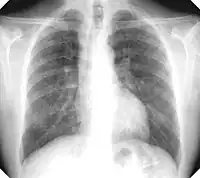

There are three key elements to the diagnosis of silicosis. First, the patient history should reveal exposure to sufficient silica dust to cause this illness. Second, chest imaging (usually chest x-ray) that reveals findings consistent with silicosis. Third, there are no underlying illnesses that are more likely to be causing the abnormalities. Physical examination is usually unremarkable unless there is complicated disease. The examination findings are not specific for silicosis.[19]

For uncomplicated silicosis, chest x-ray will confirm the presence of small (< 10 mm) nodules in the lungs, especially in the upper lung zones. Using the ILO classification system, these are of profusion 1/0 or greater and shape/size "p", "q", or "r". Lung zone involvement and profusion increases with disease progression. In advanced cases of silicosis, large opacity (> 1 cm) occurs from coalescence of small opacities, particularly in the upper lung zones.

With retraction of the lung tissue, there is compensatory emphysema. Enlargement of the hilum is common with chronic and accelerated silicosis. In about 5–10% of cases, the nodes will calcify circumferentially, producing so-called "eggshell" calcification. This finding is not pathognomonic (diagnostic) of silicosis. In some cases, the pulmonary nodules may also become calcified.

Usually resulting from long-term exposure (10 years or more) to relatively low concentrations of silica dust and usually appearing 10–30 years after first exposure.[22] This is the most common type of silicosis. Patients with this type of silicosis, especially early on, may not have obvious signs or symptoms of disease, but abnormalities may be detected by x-ray. Chronic cough and exertional dyspnea (shortness of breath) are common findings. Radiographically, chronic simple silicosis reveals a profusion of small (<10 mm in diameter) opacities, typically rounded, and predominating in the upper lung zones.

Silicosis that develops 5–10 years after first exposure to higher concentrations of silica dust. Symptoms and x-ray findings are similar to chronic simple silicosis, but occur earlier and tend to progress more rapidly. Patients with accelerated silicosis are at greater risk for complicated disease, including progressive massive fibrosis (PMF).